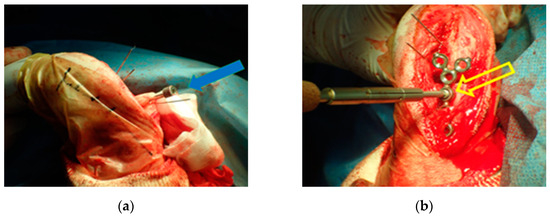

2.5. Surgery and Evaluation